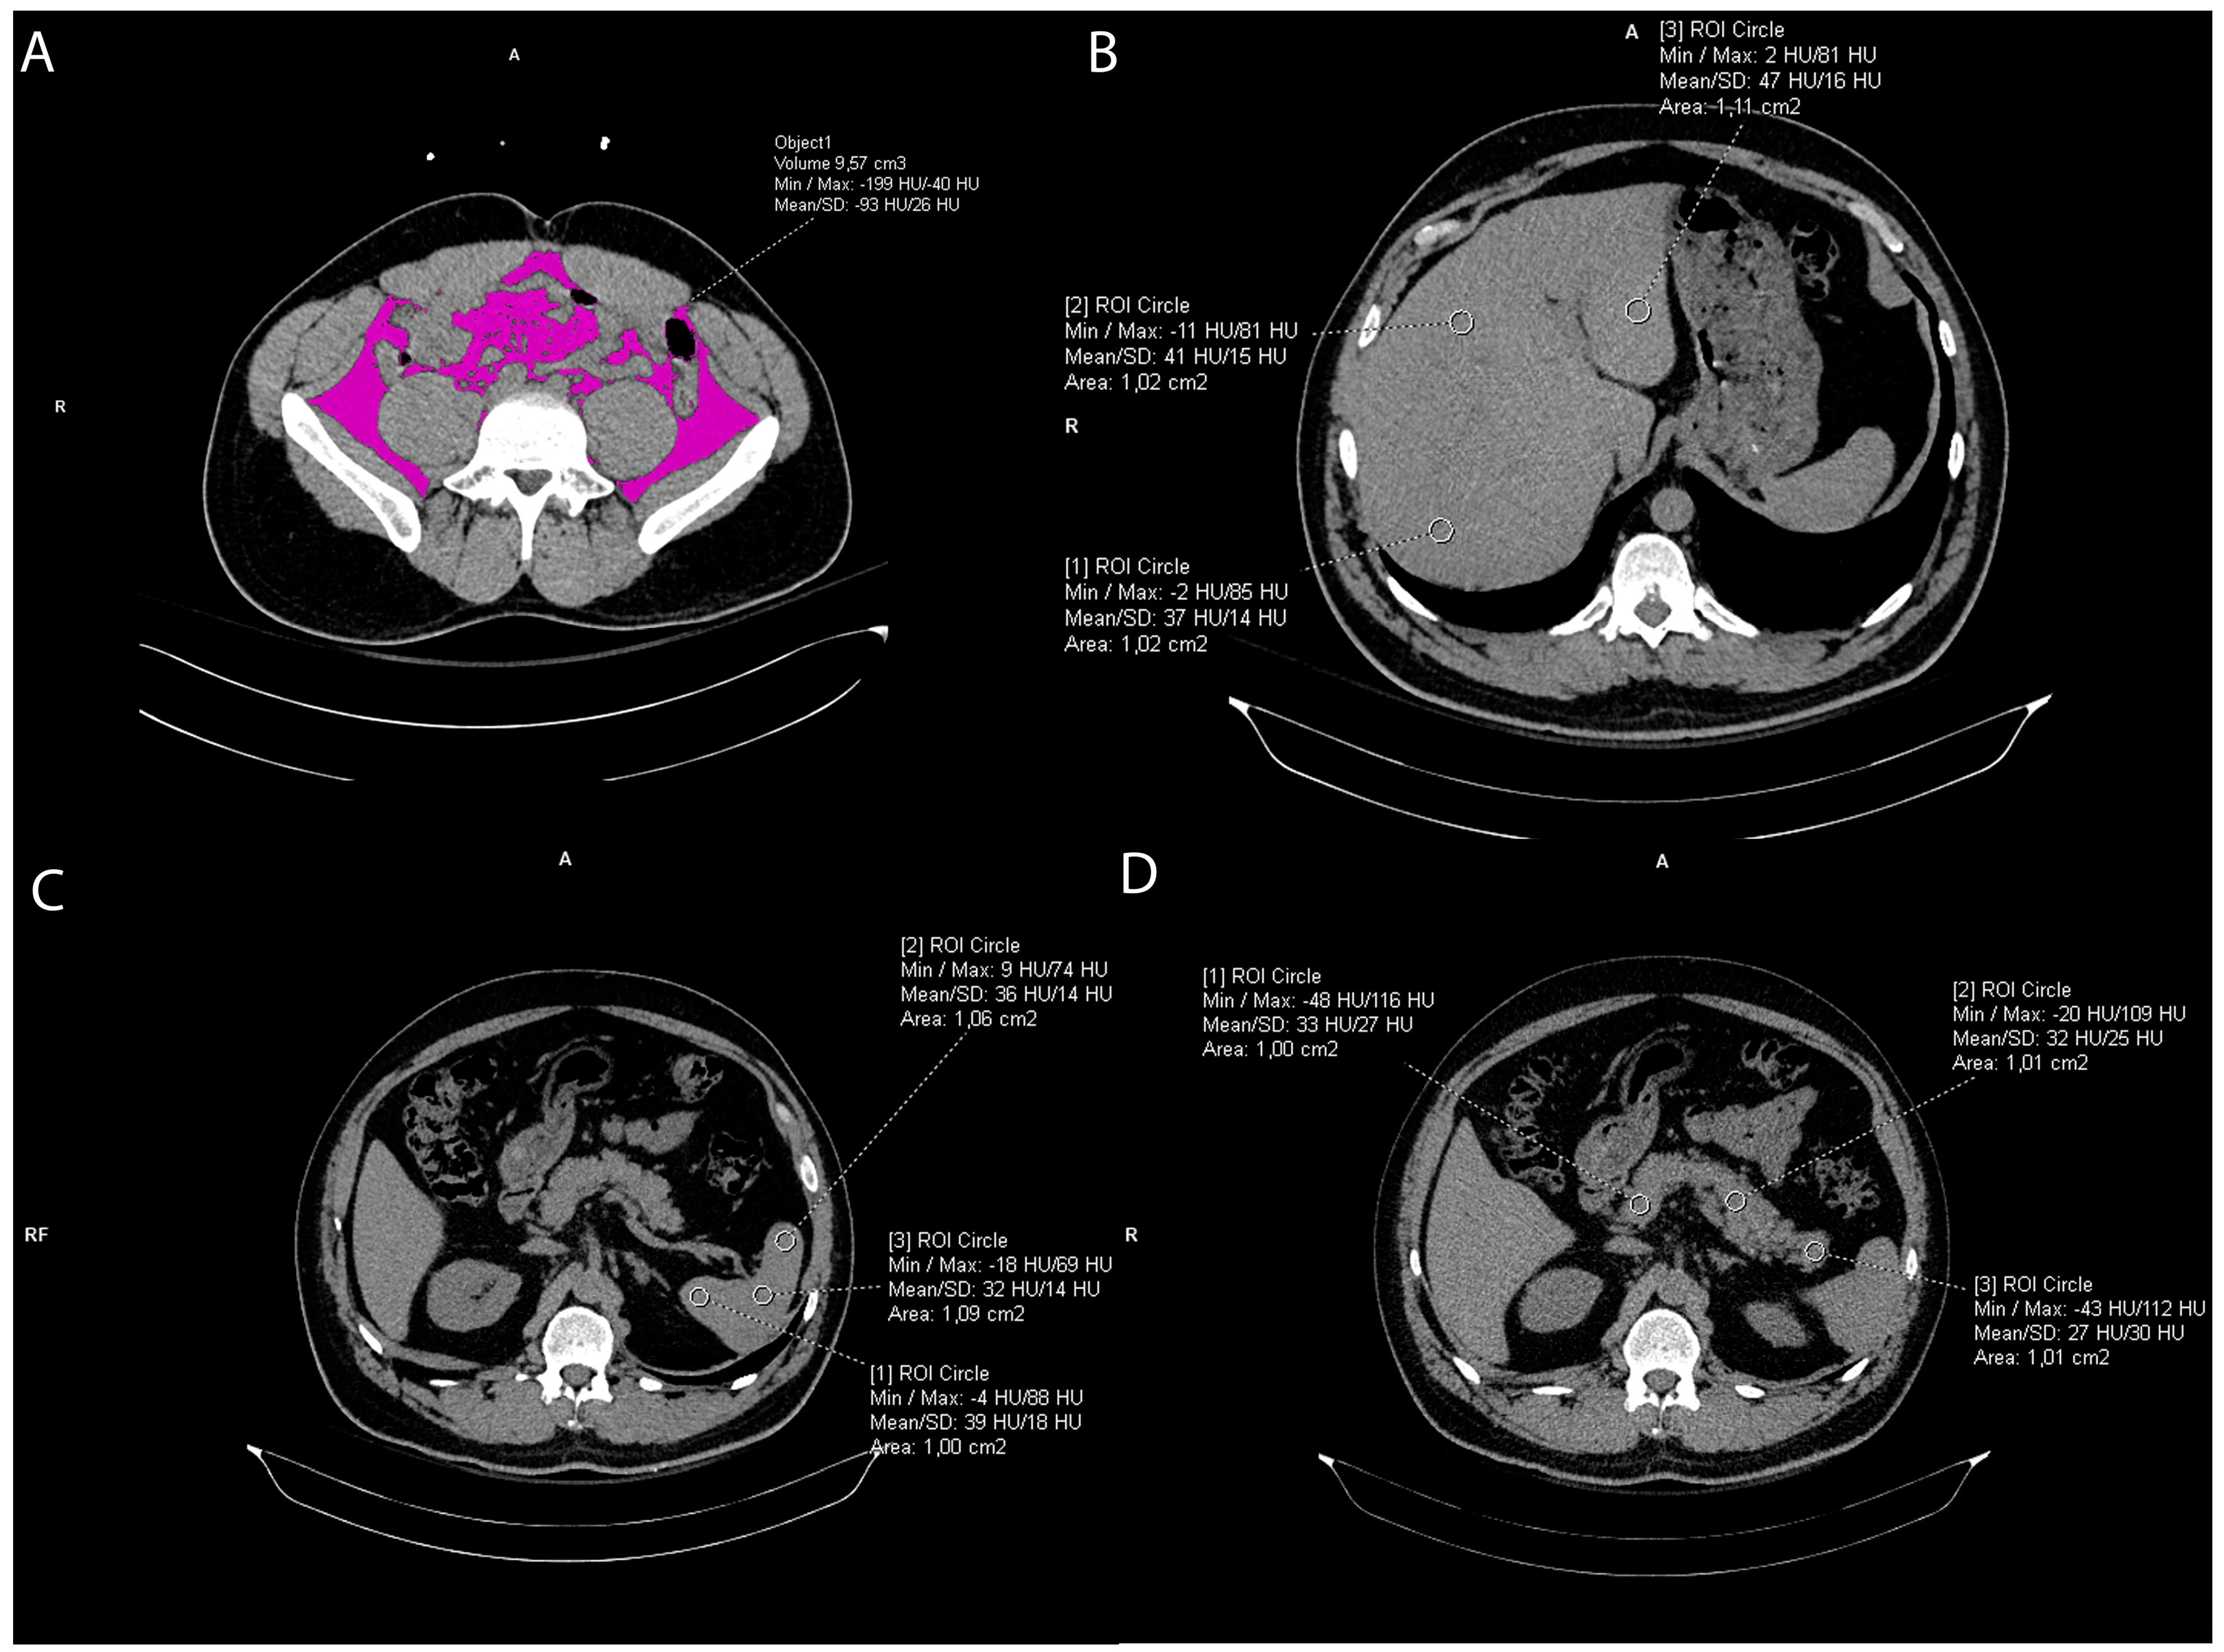

2.2. Visceral Fat Measurement

The intraabdominal visceral fat volume, expressed in cm3, was measured on the pre-contrast CT scan by manually drawing a line along the inner contour of the abdominal muscles which surround the abdominal cavity at the umbilical level. The CT value of fat tissue attenuation from −200 to −40 HU was semi-automatically segmented within the drawn line and the visceral fat volume was automatically calculated using the Siemens software syngo.via VB60A_HF08 (Figure 2).

Figure 2. Representative axial CT images showing visceral fat volume calculation (A), liver attenuation measurement (B), spleen attenuation measurement (C), and pancreas attenuation measurement (D).

2.3. Liver and Spleen Attenuation Measurement

Liver CT attenuation was estimated by drawing three round regions of interest (ROI) of the approximately same size, 1 cm2, at the portal vein level within the left lobe, right anterior lobe, and right posterior lobe of the liver, respectively. All ROIs were carefully distributed in the liver parenchyma and the biliary, vascular, and extrahepatic structures were excluded. (Figure 2). The final liver attenuation measure was an average Hounsfield Unit (HU) at the three measurements sites. Spleen attenuation was similarly obtained by averaging three manually placed round ROIs (approximately 1 cm2) at three different areas of the same slice (Figure 3). The attenuation index, the liver-to-spleen attenuation ratio (L/S), was calculated by dividing average liver with average spleen attenuation, fi L is the hepatic attenuation and S is the splenic attenuation [21,22]. The index was used as a measure of liver fat accumulation (ectopic fat).

2.4. Pancreas Attenuation Measurement

Five ROIs were drawn over the uncinate process, the head, neck, body, and tail of the pancreas (Figure 2), while three ROIs were drawn in the spleen, as previously mentioned (Figure 2), [23,24]. In both organs, a circular ROI of 1 cm2 was drawn [24,25]. To ensure reproducibility of the measurements, the ROIs were manually placed in order to avoid vessels and parenchymal calcifications. An average of the ROIs was calculated and then the pancreas-to-spleen attenuation ratio (P/S) was determined by dividing the mean attenuation value of the pancreas with the mean attenuation value of the spleen. The pancreas-to-spleen attenuation ratio significantly correlated with pancreatic fat accumulation (pancreatic steatosis, ectopic fat) proven histopathologically [24,25,26,27,28].